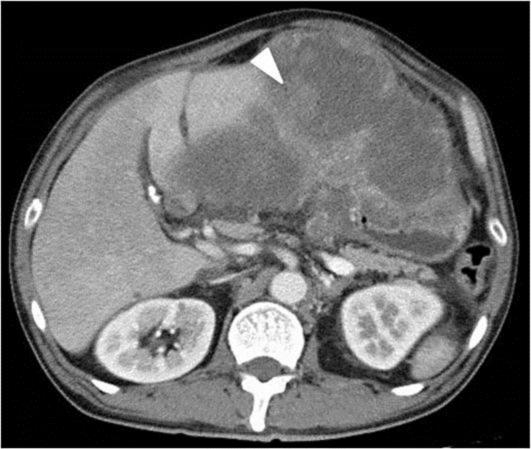

A 61-year-old Japanese male was seen at an outside hospital with abdominal pain and distention. An intraabdominal mass was found on abdominal computed tomography (CT), and he was referred for further evaluation. He was afebrile, with mild tenderness in the upper abdomen and massive distention. Routine blood work showed severe inflammation and anemia. Repeat CT showed a large solitary heterogeneous mass, 25 cm in diameter, in the left upper quadrant with evidence of intratumoral bleeding and irregular enhancement peripherally. There was no clear distinction between the mass and the peripheral organs. Surgery was performed with persistent anemia and exacerbation of abdominal pain. Lateral segmentectomy, total gastrectomy, cholecystectomy and partial resection of the diaphragm and parietal peritoneum were performed. The final diagnosis was cholangiocarcinoma with sarcomatous changes. On the 16th postoperative day a CT scan revealed recurrent tumor. The patient died on the 34th postoperative day from rapid tumor progression.